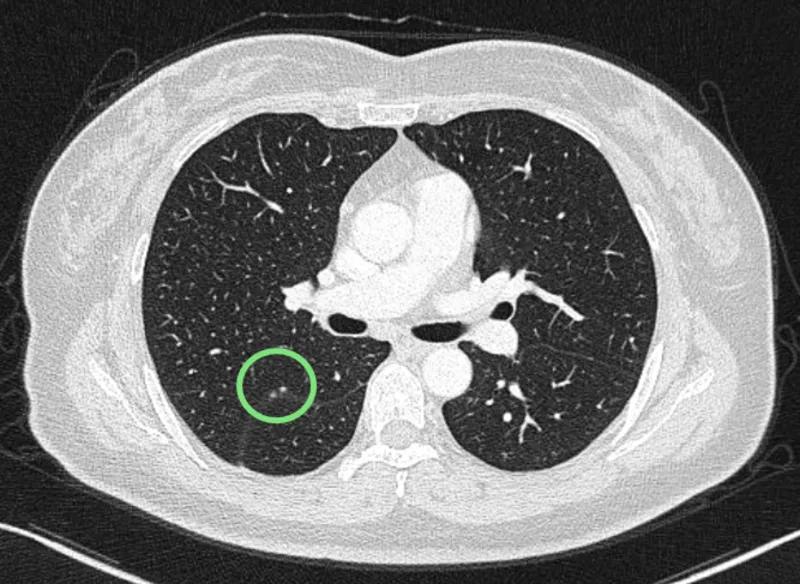

可见是右下肺达近5厘米的肿块,并上叶磨玻璃结节以及斜裂、水平裂多发微小结节。影像是如何的呢?

到底该如何考虑?下一步该如何决策?我的意见是:右下叶红色圈起来的考虑是肺癌,浸润性腺癌可能性大;右上叶磨玻璃结节粉色圈起来的考虑原位癌或不典型增生可能性大;绿色圈起来的基本上是叶裂处,从密度来看更像良性,但因为有右下叶的病灶在,也可能是种植转移,但术前较难确定。PET-CT可以考虑,但也有假阴性或假阳性。个人意见是如果没有远处其他确切转移,建议胸腔镜下探查,如果微小实性结节非转移性,则右下肺癌仍能手术的。如果真若是转移,也可取行病理依据,并送基因检测与免疫组化等检查,而单孔胸腔镜下探查下创伤小,恢复快,当然若不是转移,顺便镜下行右下叶切除并清扫淋巴结就行。